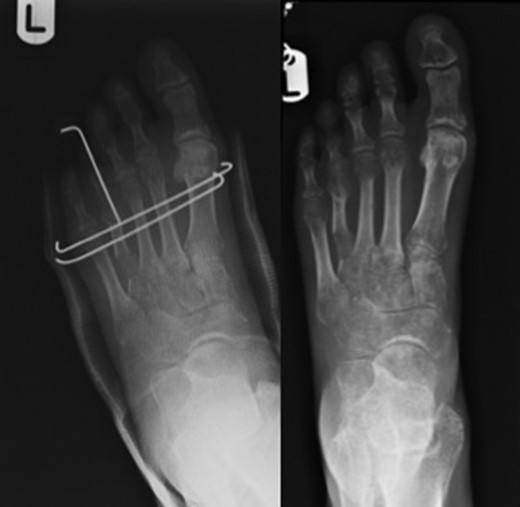

Brachymetatarsia is defined as one metatarsal ending 5 mm or more proximal to the parabolic arch of the other adjacent metatarsals [1, 2]. A shortened metatarsus can be congenital (Fig. 1) or acquired through trauma, infections, tumours or iatrogenic.

Pre-operative images on the left alongside x-rays on the right depicting congenitally short fourth toes.

Pre-operative image on the left with image on the right showing successful lengthening.